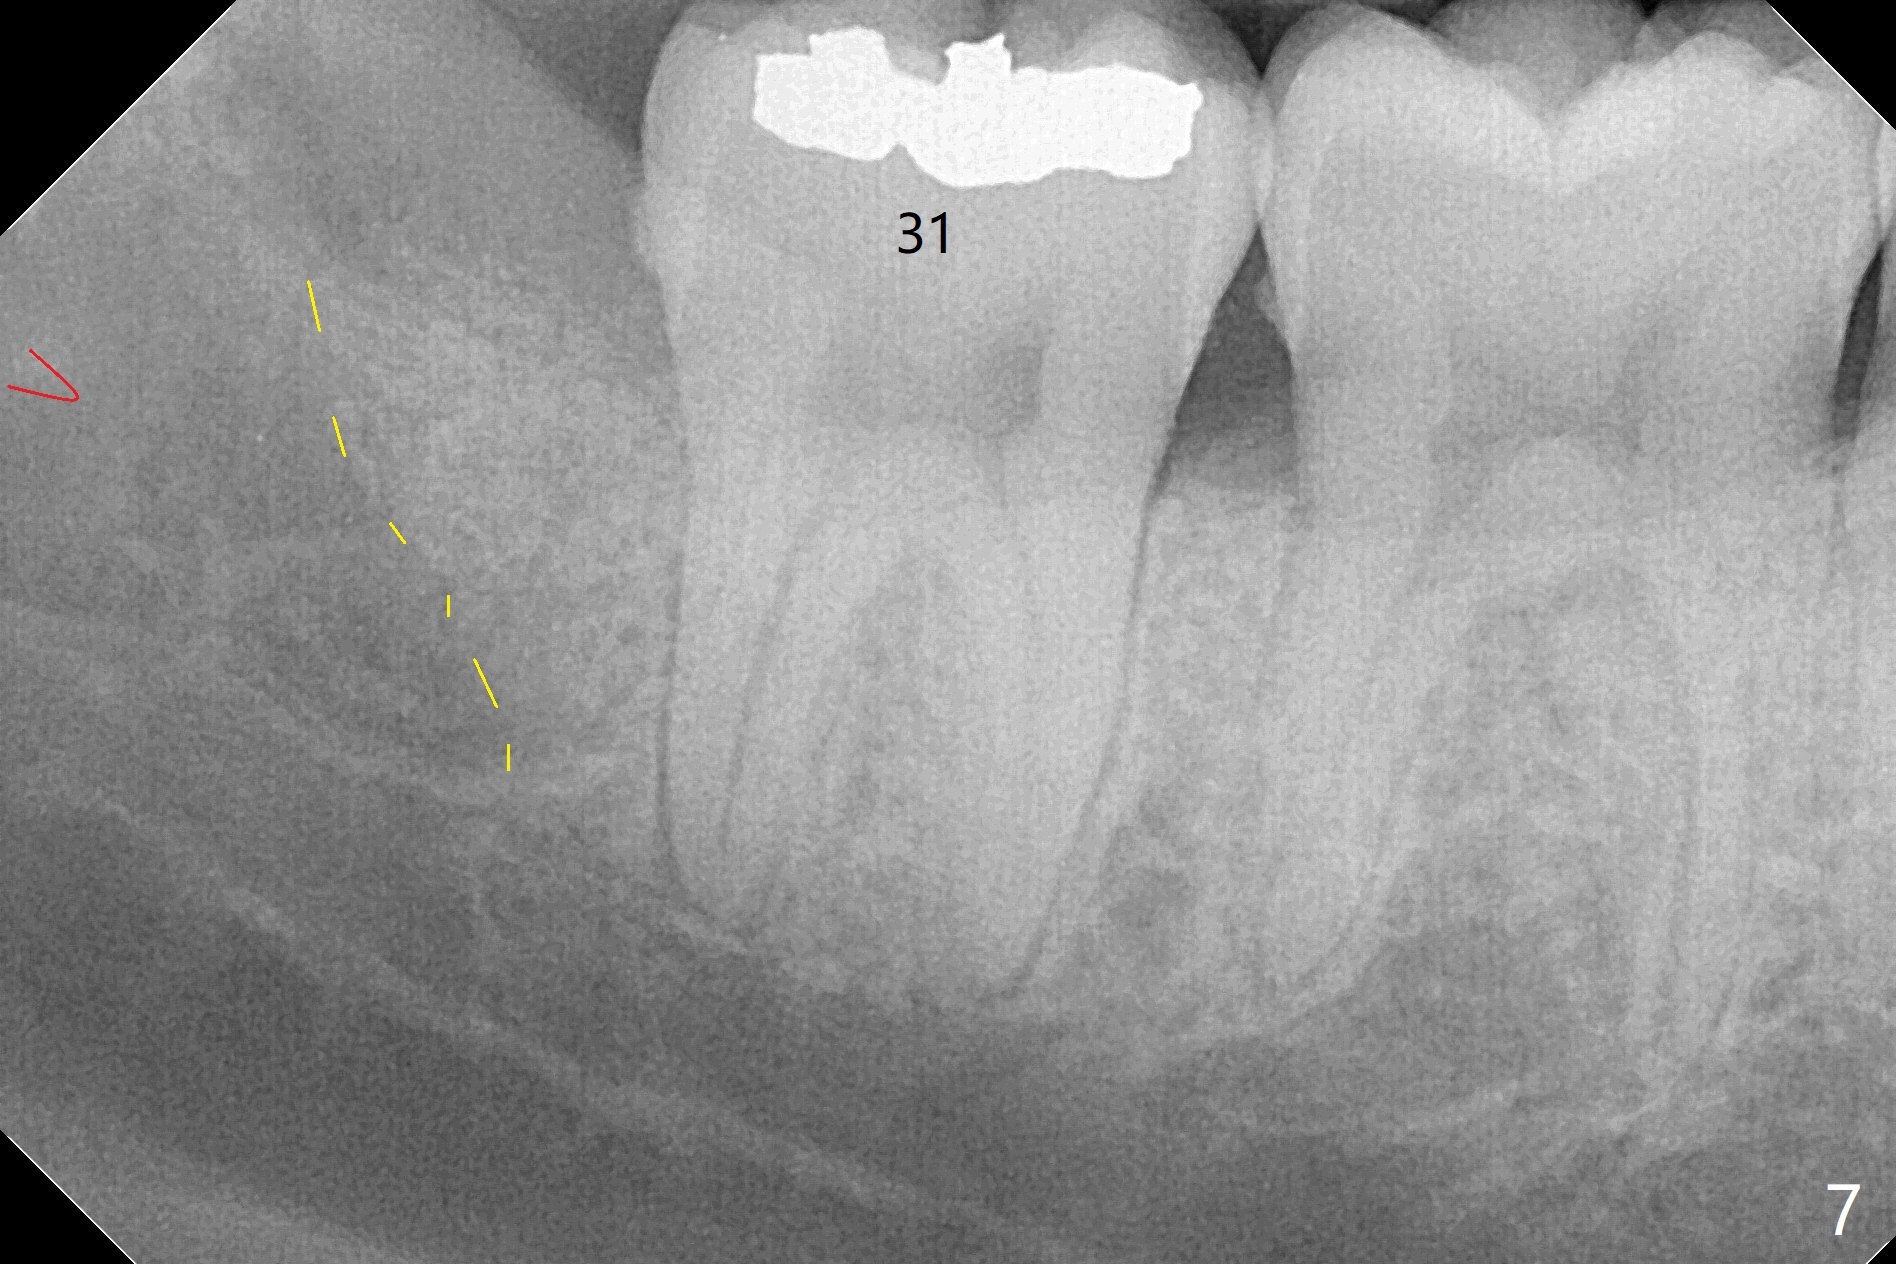

When the tooth #17 is extracted (Fig.9; 23 years old), collagen plug is inserted into the root portion of the sockets (Fig.10: 1 (white outline)), Vanilla graft is placed against the distal surface of #18 (2 (red outline)) and Osteogen plug (3 (green outline)) is placed coronally (3 steps). There is no bony defect associated with the distal surface of the tooth #18 immediate postop (Fig.11 (red dashed line: bone graft)). The wound heals in 2 weeks.